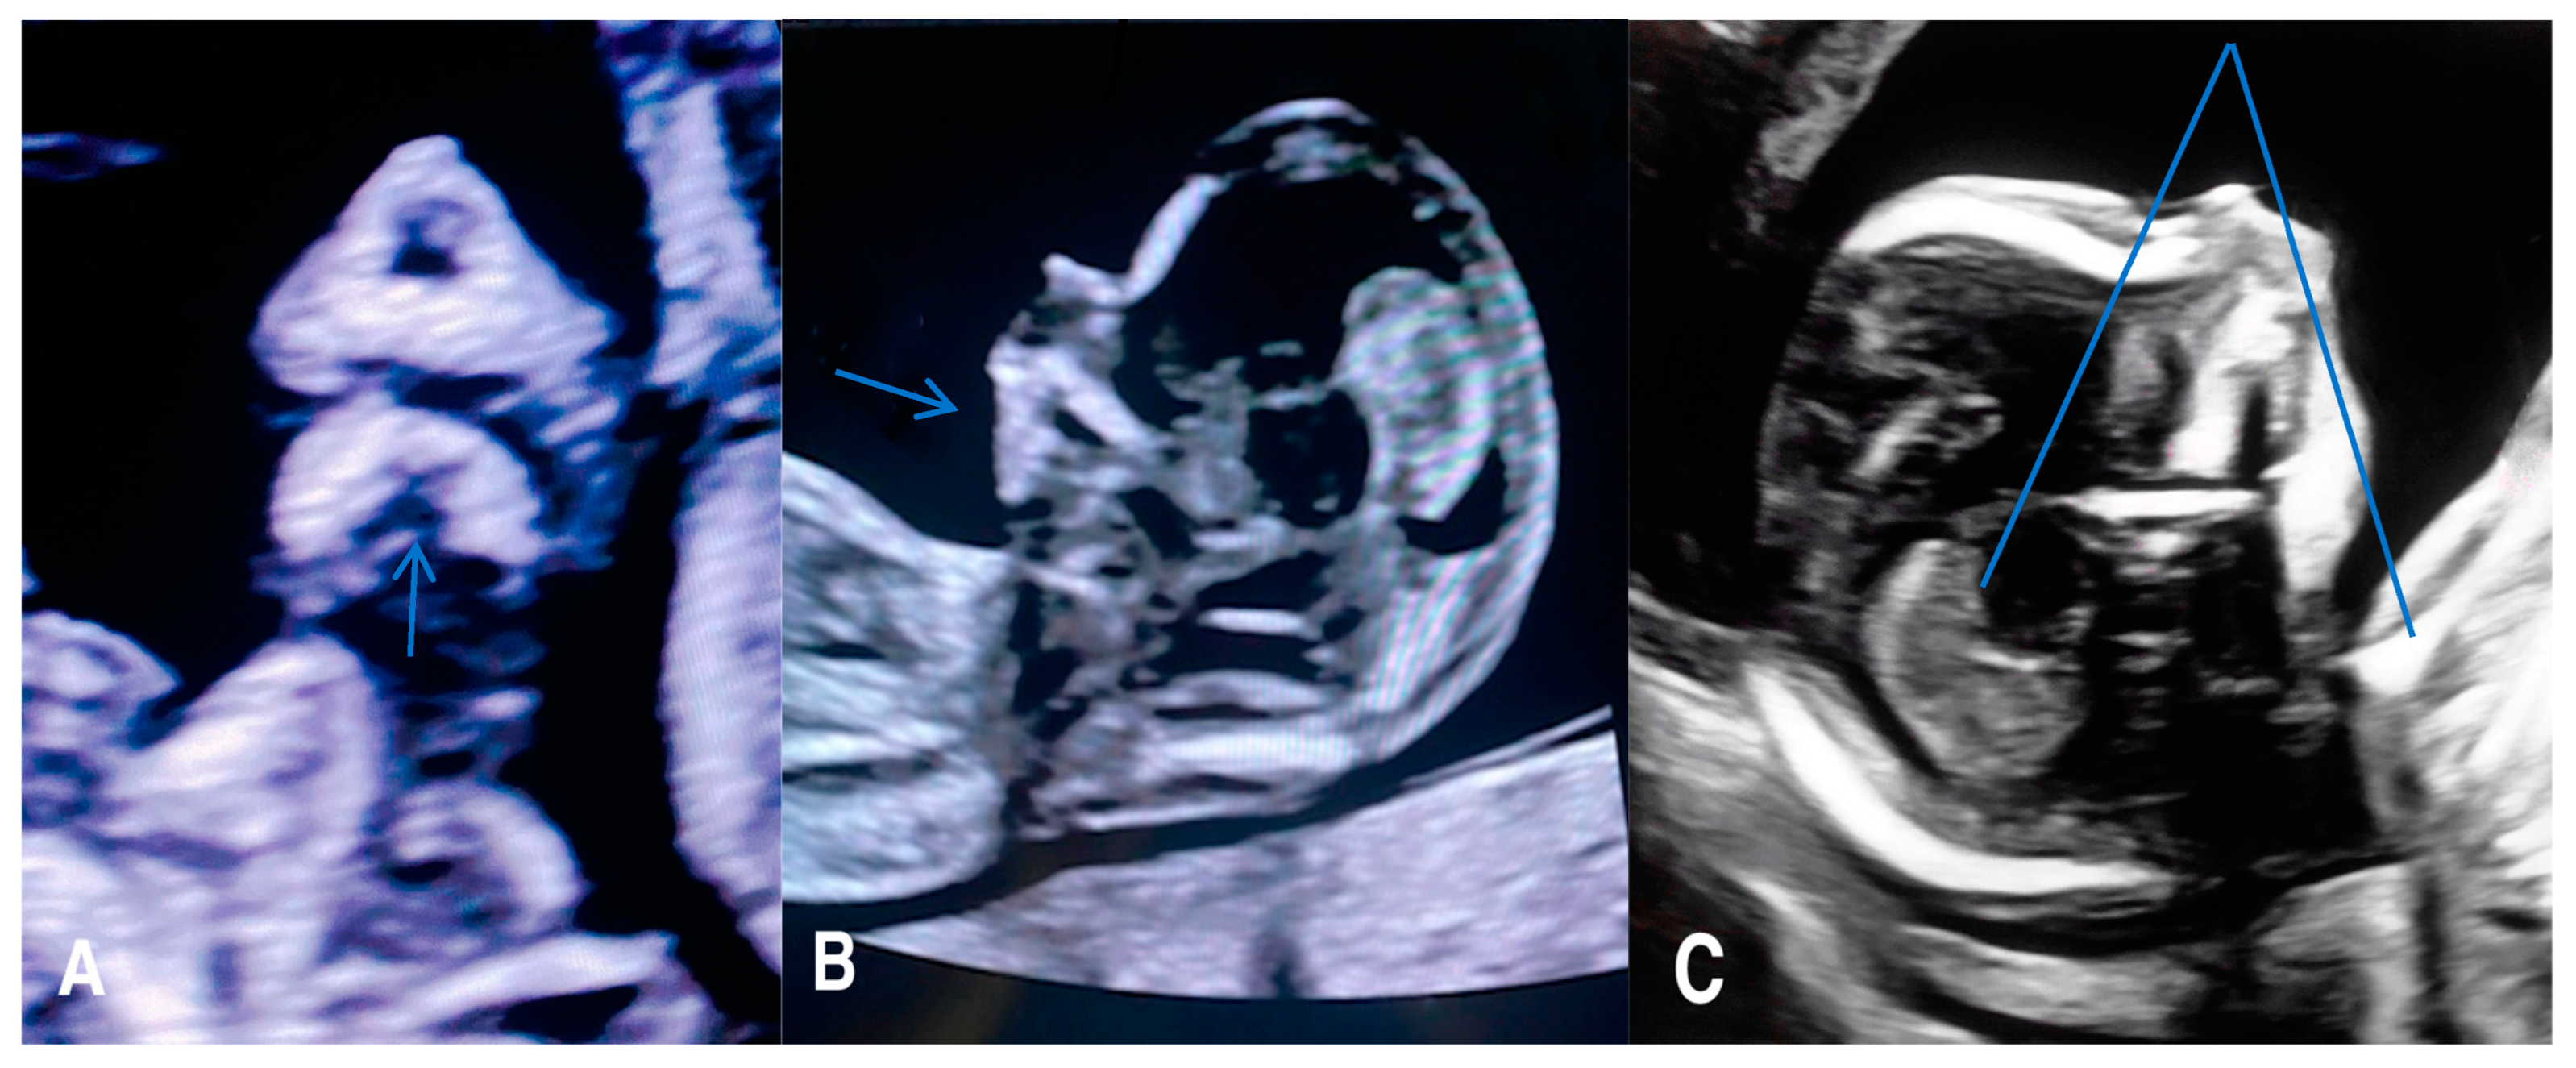

Micrognathia indicates a small chin secondary to underdevelopment of the mandible, while retrognathia means as abnormal posterior placement of the mandible (Figure 2).

Figure 2.

(A) A 2D coronal scan of the postnasal triangle of a 12 week old fetus where absence of the regular gap (see arrow) within the mandible indicates micrognathia and/or retrognathia. (B) Axial scan of the same fetus where the arrow indicating underdevelopment and/or posterior displacement of the chin (micrognathia and/or retrognathia). (C) Axial scan of the same fetus of 18 weeks with an inferior facial angle (IFA) (blue lines) of 45 degrees, diagnostic of micrognathia and/or retrognathia.

These two findings pose challenges in differentiation and can manifest concurrently. Micrognathia is frequently linked to syndromes or other abnormalities. Notable syndromes associated with micrognathia/retrognathia include Treacher Collins, Pierre Robin sequence, Stickler, and 22q11.2 deletion syndrome. Ultrasound imaging plays a crucial role, particularly the mid-sagittal profile, which helps evaluate the abnormal jaw position.

Numerous quantitative methods are considered for diagnosing micrognathia, utilizing both 2D and 3D ultrasound. Rotten et al. defined two-dimensional and three-dimensional sonographic parameters to objectively diagnose retrognathia and micrognathia between 18 and 28 weeks of gestation. Their findings indicated that retrognathia is associated with a decrease in the inferior facial angle (IFA). Therefore, a diagnosis of micrognathia/retrognathia can be established when the IFA measures less than 49.2°. This angle is defined by an orthogonal line to the vertical section of the forehead at the level of the nasal bone synostoses and a line connecting the chin’s tip to the anterior limit of the protrusive margin [30]. Despite these developments, diagnosing micrognathia/retrognathia remains challenging during both the second and the first trimesters. To address this, Sepulveda et al. proposed using ultrasound scans in the coronal view of the retronasal triangle to assess the midface during the first trimester. Their study revealed that a normal fetus exhibits a gap between the two mandibular bones, referred to as the mandibular gap. In contrast, fetuses with micrognathia/retrognathia lack this gap, or the mandible cannot be identified at this level. However, further research is necessary to determine the sensitivity and specificity of the first-trimester retronasal triangle view to detect cleft palate. Consequently, an early-second-trimester targeted scan remains a complementary diagnostic examination to consider [31].